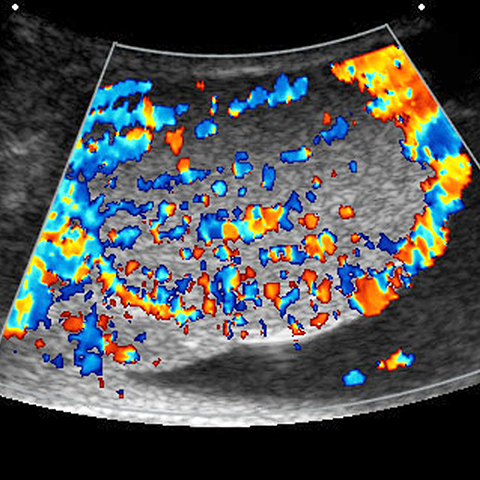

26-year-old-male presents with scrotal swelling and pain. [2 of 2]